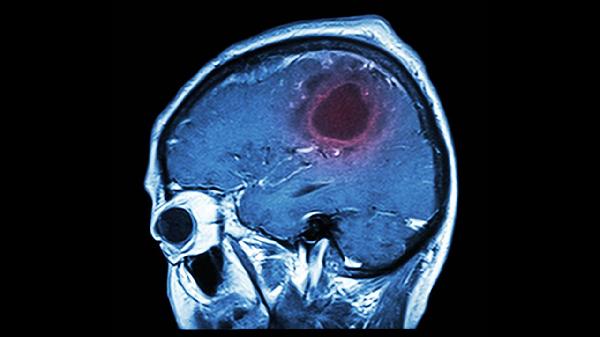

3、影像学特征:

CT检查中脑出血表现为高密度影,脑栓塞可见责任血管供血区低密度灶,常伴出血性梗死;脑血栓形成的梗死灶多呈楔形,与动脉分布区一致。MRI的DWI序列对早期脑梗死具有更高敏感性。